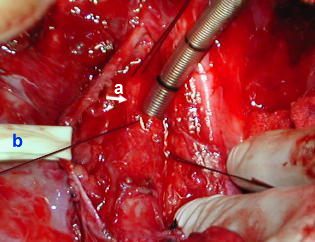

Identificación de la lesión

• La zona estenótica traqueal se identifica por la disminución del diametro anteroposterior, la consistencia firme de la pared y la deformidad de los anillos traqueales a ese nivel, en este paciente se confirmó la localización mediante broncoscopia y punción traqueal con aguja fina (22) en los bordes estenoticos distal y proximal. posteriormente se procedió a colocar puntos de refencia laterotraqueales proximal y distal de la zona a resecar, aproximadamente unos 2,5 cm de traquea torácica.

• - (a) - Nervio neumogastrico vago derecho. (aislado y a la izquierda de las referencias).

- (b) -Lesión estenosante de 2.5 cm en traquea torácica, Referencias traqueales superiores e inferiores.